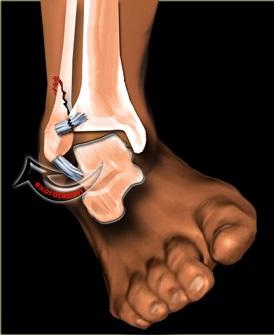

· 踝关节复合体可分为三部分:距小腿关节(踝关节)、距跟舟关节和距下关节。距小腿关节(TC)由三块骨头和一个复杂的韧带装置组成。胫骨、腓骨和距骨通过侧副韧带和下胫腓韧带复合体连接。¹

损伤机制

胫腓骨骨折的损伤机制根据所受能量大小差异显著,主要分为两类:

低能量损伤: 通常包括平地跌倒和运动损伤。这种情况下,腓骨常因应力或过度使用而受损,尤其是在重复性运动或活动量突然增加时。这类损伤可能导致应力性骨折或腓骨轻微骨折,常见于跑步者或运动员。

高能量损伤: 与更严重的创伤相关,如机动车事故、行人被车辆撞击或枪伤。这种情况下,腓骨遭受突然、猛烈的冲击,可能导致更严重的骨折。这些骨折通常较复杂,并可能伴有周围软组织和其它骨骼的损伤。